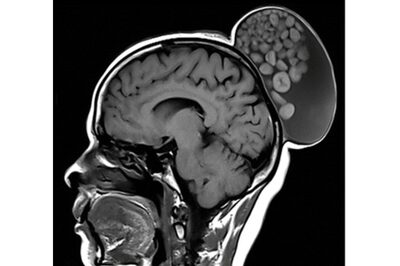

An MRI scan showed the cyst on the back of the woman's head, like a fleshy made hair bun